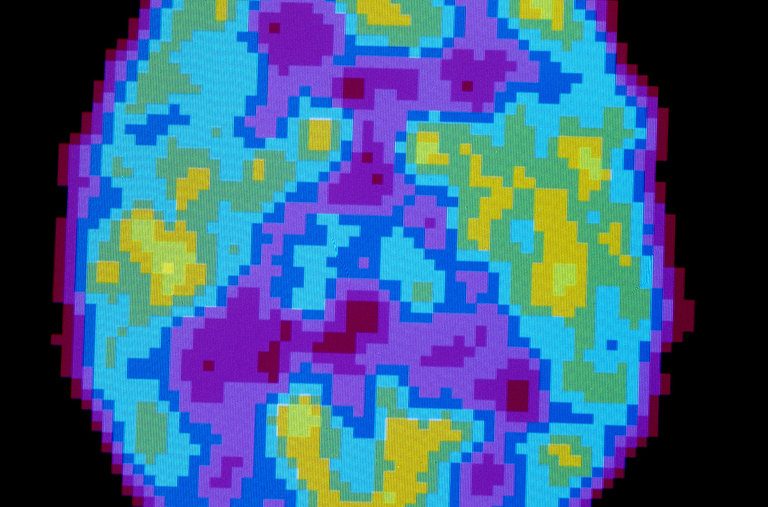

Other evidence comes from the electric waves released by the brain. During deep sleep, the waves slow down. Dr. Tononi and Dr. Cirelli have argued that shrinking synapses produce this change.

其他证据来自大脑释放的电波。在深度睡眠期间,电波减慢。 托诺尼博士和奇雷利博士认为,这种变化是由突触缩小带来的。